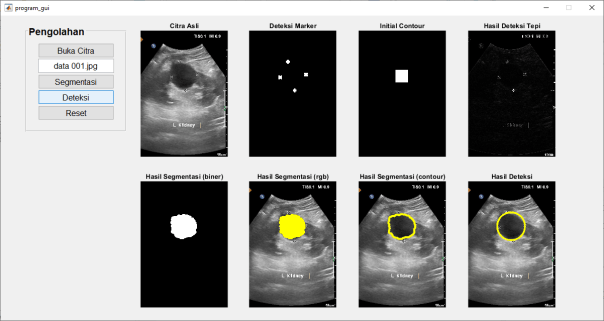

Pengolahan Citra Ultrasonography: Memperbaiki Kualitas Gambar

Pengolahan citra ultrasonography adalah langkah penting dalam memastikan bahwa gambar-gambar yang dihasilkan memiliki kualitas yang optimal. Berbagai teknik pengolahan digunakan untuk meningkatkan kejelasan gambar, mengurangi noise, dan menyoroti fitur-fitur yang penting untuk diagnosis. Dengan pengolahan citra yang tepat, dokter dapat mendapatkan informasi yang lebih akurat tentang kondisi pasien.

Mendeteksi Tumor dengan Ultrasonography

Ultrasonography juga digunakan untuk mendeteksi tumor dalam berbagai organ tubuh. Meskipun tidak selalu sepevoelenctif MRI atau CT scan dalam mendeteksi tumor kecil atau dalam organ yang terletak di belakang tulang, ultrasonography tetap menjadi pilihan di beberapa kasus karena biayanya yang lebih rendah dan tidak adanya paparan radiasi. Beberapa teknik pengolahan citra ultrasonography yang digunakan dalam mendeteksi tumor meliputi:

- Enhancement: Enhancement digunakan untuk meningkatkan kontras antara tumor dan jaringan sekitarnya, membuat tumor lebih mudah terlihat pada gambar ultrasonography.

- Elasography: Elasography adalah teknik yang digunakan untuk mengevaluasi kekakuan atau elastisitas jaringan, yang dapat membantu dalam membedakan tumor dari jaringan normal.

- Targeted Imaging: Dalam beberapa kasus, agen kontras dapat diberikan kepada pasien sebelum pemeriksaan ultrasonography untuk meningkatkan visibilitas tumor.

- Segmentasi: Segmentasi adalah proses membagi gambar medis menjadi beberapa bagian yang homogen berdasarkan kriteria tertentu. Ini dapat membantu dalam memisahkan struktur anatomi atau lesi dalam gambar medis untuk analisis lebih lanjut.